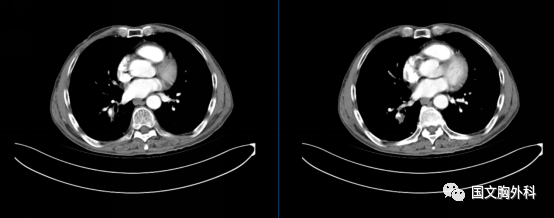

治療后↓

患者于吉林國文醫(yī)院順利完成右肺下葉切除術(shù)手術(shù)治療,保留了右肺的中葉。

更幸運(yùn)的是原先肺癌切下來后,顯微鏡下都找不到癌細(xì)胞,這真是奇跡。來到國文醫(yī)院診療,真是得病后不幸中的萬幸。